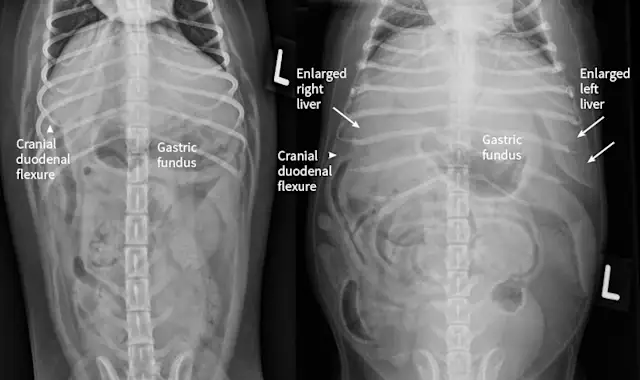

Right lateral radiographs of a clinically normal dog (A) and an 11-year-old neutered male dachshund with diabetes mellitus (B). The dog with diabetes mellitus has a pendulous abdomen and an enlarged liver (ie, hepatomegaly) with rounded margins that extend caudal to the costal arch (B; arrows). The gastric axis (solid lines; aligned with the gastric fundus dorsally to the antrum ventrally) is parallel to the ribs in the clinically normal dog but caudally displaced in the dog with hepatomegaly. Common differential diagnoses for generalized hepatomegaly are vacuolar hepatopathy due to endocrinopathies or other metabolic disease (eg, lipidosis), infectious and noninfectious inflammatory disease, neoplasia, storage disease, and venous congestion.